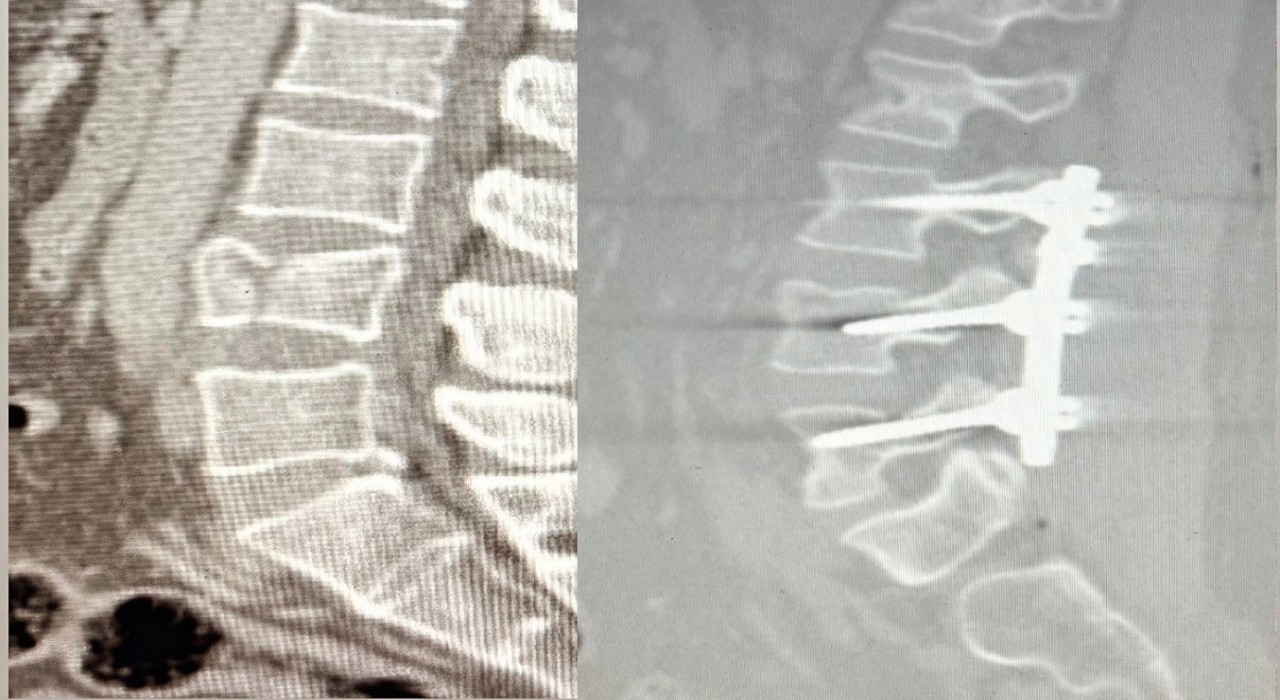

Patnos Devlet Hastanesi’nde ilk kez gerçekleştirilen lomber stabilizasyon ameliyatı sonrası, çökme kırığı yaşayan hasta kısa sürede ayağa kalktı.

Ağrı’nın Patnos ilçesinde 2,5 metre yüksekten düşen 41 yaşındaki Tekin Maskar, bel bölgesindeki kırık nedeniyle acil servise başvurdu. Yapılan tetkiklerde omurgada çökme kırığı tespit edilmesi üzerine hasta, ortopedi uzmanları Op. Dr. Muhammed Serpi ve Op. Dr. Mustafa İçen tarafından ameliyata alındı.

Ameliyat sırasında bel bölgesindeki omurların sabitlenmesini sağlayan lomber stabilizasyon tekniği kullanıldı. Hastane tarihinde ilk kez gerçekleştirilen bu operasyon sonrası hasta sağlıklı şekilde yürümeye başladı.